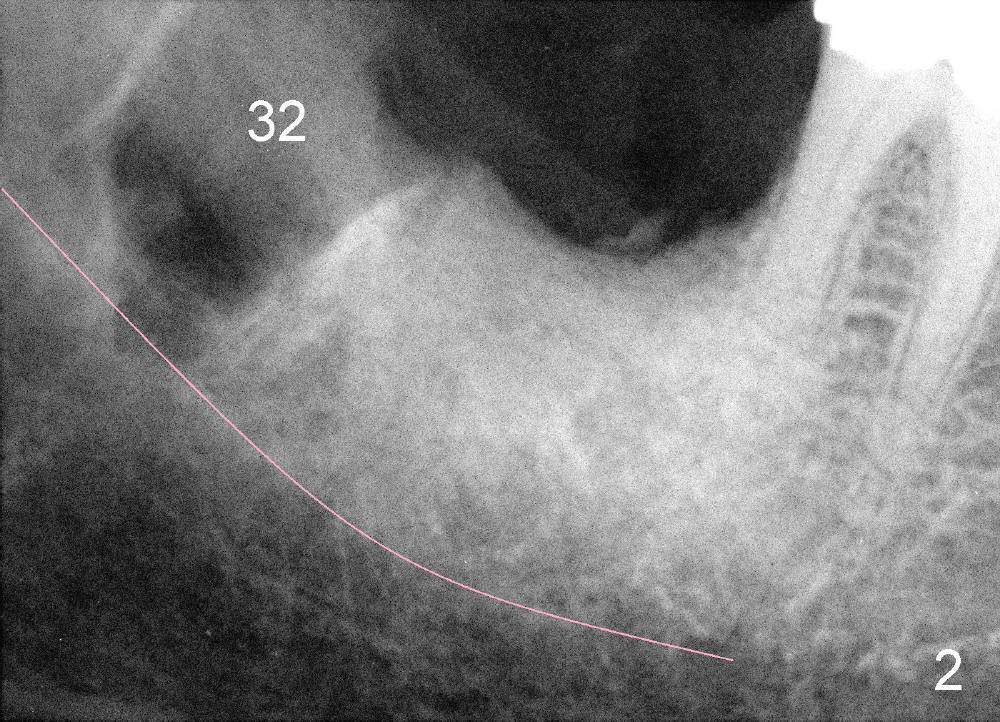

Mrs. Hwang in her sixties has had periodontal disease in her lower right 2nd molar (Fig.1 *). Three years later, both the 2nd and 3rd molars are extracted (Fig.2; pink: the upper border of the inferior alveolar canal). Four months after extraction, the patient returns for implant placement at the site of #31 (Fig.3, 4). The socket of the 2nd molar is outlined in yellow in Fig.3.